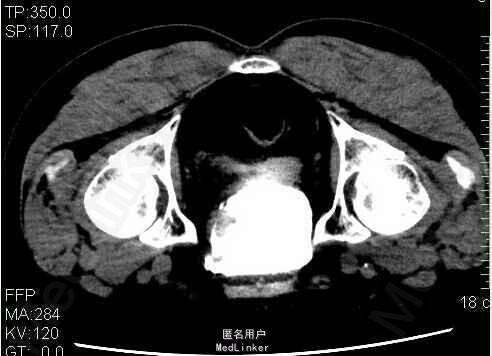

2、外院B超示:膀胱左侧壁可见一38x28mm低回声不规则包块,内见血流信号。现为进一步诊治,门诊拟以“膀胱占位性病变”收入我科。患者入院后双肾CTU及盆腔CT示:膀胱所见,考虑膀胱癌并累及全层;盆部、双侧腹沟股多发稍大淋巴结影 3、查体:腹平软,双侧上中输尿管点无压痛,膀胱区无压痛。双侧腹股沟区未触及肿物,尿道外口未见异常,阴囊无水肿,双睾丸可触及,肛周皮肤无红肿。直肠指检:肛门括约肌正常,前列腺不大,无触痛,表面光滑,质韧,边缘清楚,中央沟存在,未触及明显结节,指套未见染血。